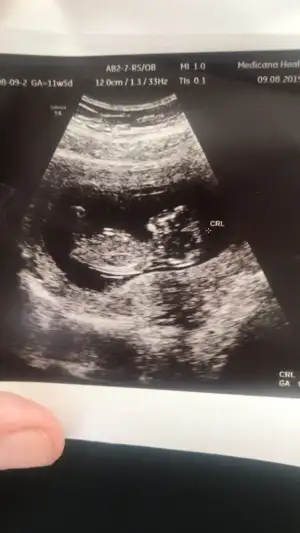

11+5 dr erken söylemiş saglıkla gelsin minoşunuz .Bu da teoriyi destekliyor mu bilmiyorum ama son ultrasonu. Yerinde durmuyor çiçeğimmm![]()

Evet ama ölçümde 12+4 çıktı tombulum11+5 dr erken söylemiş saglıkla gelsin minoşunuz .bende adanadan